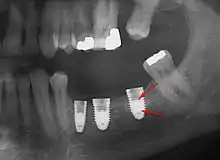

Bone loss (peri-implantitis) on implants over 7 years in a heavy smoker

Fixture show

Fracture of abutment screws (arrow) in 3 implants required removal of the remainder of the screw and replacement.